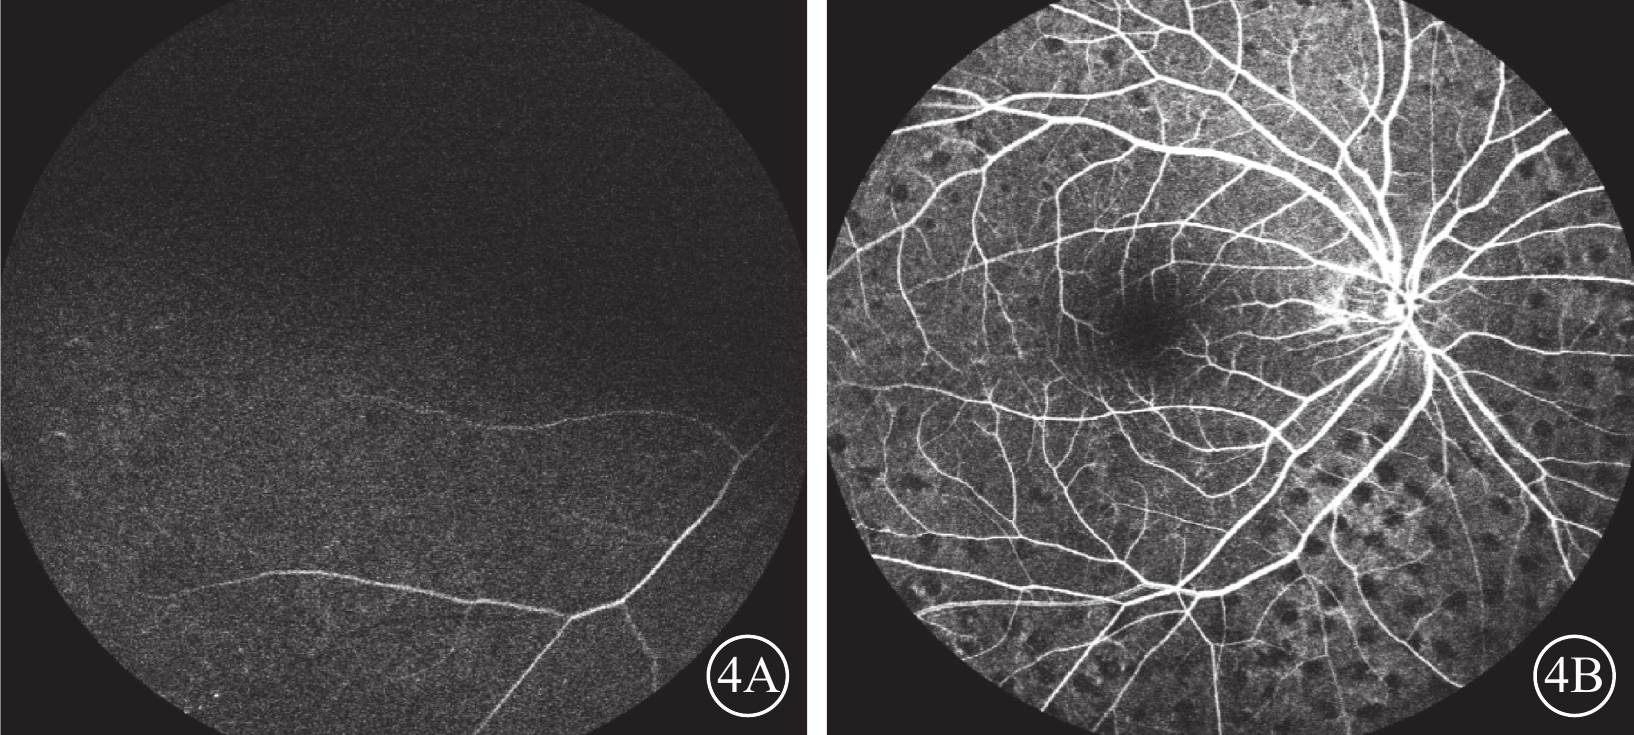

患者男,65歲。因右眼視物不見1周于2016年10月20日來我院就診。1周前無意中發現右眼視物不見,無眼紅、痛、畏光、流淚;自行使用芐達賴氨酸(商品名:莎普愛思)滴眼液滴眼無效而就診于外院。診斷為右眼新生血管性青光眼(NVG)?右眼視網膜病變(性質?);雙眼老年性白內障。既往高血壓病史8年,口服藥物治療。否認糖尿病、冠心病等其他全身病史。眼科檢查:右眼視力光感/眼前;左眼視力0.6,不能矯正。右眼眼壓17.3 mmHg(1 mmHg= 0.133 kPa),左眼眼壓12.7 mmHg。右眼前房深淺正常,周邊前房1 角膜厚度;瞳孔藥物性散大,邊緣全周可見虹膜新生血管(NVI),無后粘連;晶狀體混濁;玻璃體輕度混濁。眼底視盤邊界清楚,顏色橘紅,血管走形及比例基本正常;視網膜可見散在點片狀出血及片狀棉絨斑,黃斑中心凹反光不清(圖1)。左眼除晶狀體混濁、玻璃體輕度混濁,黃斑中心凹反光不清外,其余眼前節及眼底檢查未見明顯異常。熒光素眼底血管造影(FFA)檢查,右眼脈絡膜背景熒光充盈遲緩,視網膜動靜脈循環時間明顯延長(圖2)。光相干斷層掃描檢查,右眼后極部視網膜增厚,視網膜內層間反射信號大部分增強;左眼黃斑中心凹形態不規則。彩色超聲多普勒血流成像(CDFI)檢查,雙側頸總動脈、頸內動脈多發斑塊;右側頸內動脈管腔狹窄,約70%~99%(圖3)。頸動脈CT血管造影(CTA)檢查,顱內動脈硬化,可疑右側頸內動脈C1段重度狹窄;可疑兩側基底節區、右側丘腦腔隙性缺血灶。診斷:右眼眼缺血綜合征(OIS);雙眼老年性白內障;高血壓病。給予右眼玻璃體腔注射雷珠單抗0.05 ml治療。治療后3 d,視力數指/66 cm,眼壓15.0 mmHg;NVI完全消退。行右眼全視網膜激光光凝(PRP)治療。PRP治療后14 d檢查,右眼視力0.1;眼壓13.0 mmHg。轉血管外科行右側頸動脈內膜剝脫手術。手術后1個月復查,右眼視力0.4。FFA檢查,視網膜循環時間明顯改善(圖4)。

右眼治療后FFA像。4A. 12.75 s,視網膜中央動脈完全充盈;4B. 18.57 s,視網膜中央靜脈完全充盈

右眼治療后FFA像。4A. 12.75 s,視網膜中央動脈完全充盈;4B. 18.57 s,視網膜中央靜脈完全充盈

患者男,65歲。因右眼視物不見1周于2016年10月20日來我院就診。1周前無意中發現右眼視物不見,無眼紅、痛、畏光、流淚;自行使用芐達賴氨酸(商品名:莎普愛思)滴眼液滴眼無效而就診于外院。診斷為右眼新生血管性青光眼(NVG)?右眼視網膜病變(性質?);雙眼老年性白內障。既往高血壓病史8年,口服藥物治療。否認糖尿病、冠心病等其他全身病史。眼科檢查:右眼視力光感/眼前;左眼視力0.6,不能矯正。右眼眼壓17.3 mmHg(1 mmHg= 0.133 kPa),左眼眼壓12.7 mmHg。右眼前房深淺正常,周邊前房1 角膜厚度;瞳孔藥物性散大,邊緣全周可見虹膜新生血管(NVI),無后粘連;晶狀體混濁;玻璃體輕度混濁。眼底視盤邊界清楚,顏色橘紅,血管走形及比例基本正常;視網膜可見散在點片狀出血及片狀棉絨斑,黃斑中心凹反光不清(圖1)。左眼除晶狀體混濁、玻璃體輕度混濁,黃斑中心凹反光不清外,其余眼前節及眼底檢查未見明顯異常。熒光素眼底血管造影(FFA)檢查,右眼脈絡膜背景熒光充盈遲緩,視網膜動靜脈循環時間明顯延長(圖2)。光相干斷層掃描檢查,右眼后極部視網膜增厚,視網膜內層間反射信號大部分增強;左眼黃斑中心凹形態不規則。彩色超聲多普勒血流成像(CDFI)檢查,雙側頸總動脈、頸內動脈多發斑塊;右側頸內動脈管腔狹窄,約70%~99%(圖3)。頸動脈CT血管造影(CTA)檢查,顱內動脈硬化,可疑右側頸內動脈C1段重度狹窄;可疑兩側基底節區、右側丘腦腔隙性缺血灶。診斷:右眼眼缺血綜合征(OIS);雙眼老年性白內障;高血壓病。給予右眼玻璃體腔注射雷珠單抗0.05 ml治療。治療后3 d,視力數指/66 cm,眼壓15.0 mmHg;NVI完全消退。行右眼全視網膜激光光凝(PRP)治療。PRP治療后14 d檢查,右眼視力0.1;眼壓13.0 mmHg。轉血管外科行右側頸動脈內膜剝脫手術。手術后1個月復查,右眼視力0.4。FFA檢查,視網膜循環時間明顯改善(圖4)。

右眼治療后FFA像。4A. 12.75 s,視網膜中央動脈完全充盈;4B. 18.57 s,視網膜中央靜脈完全充盈

右眼治療后FFA像。4A. 12.75 s,視網膜中央動脈完全充盈;4B. 18.57 s,視網膜中央靜脈完全充盈